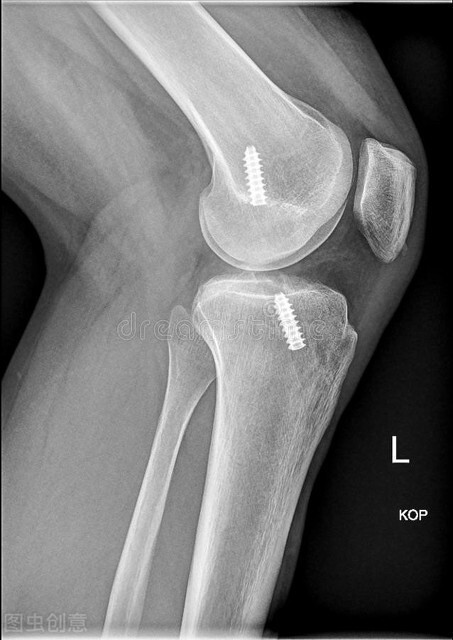

非手术治疗可能会存在反复的关节不稳、半月板撕裂和退行性关节病的风险。在前交叉韧带损伤后或前交叉韧带重建术后可能出现关节疤痕化(关节纤维化)和膝关节活动度丢失,特别是当关节活动度在术前没有恢复到完全正常范围。手术重建存在一些风险。手术的一般风险,例如感染、脉管炎、肺栓塞、血管神经损伤、疤痕;重建的前交叉韧带可能再次撕裂;或者前交叉韧带移植物愈合或重建失败导致膝关节复发性松弛。当使用一部分髌腱进行前交叉韧带重建时,也有可能出现胫骨或髌骨取材部位的骨折或者髌腱断裂。更为常见的是,取自体髌腱或自体腘绳肌腱进行移植重建的患者分别会有膝前疼痛和大腿后方疼痛。大多数患者会出现切口外侧皮肤麻木;其原因是手术损伤了隐神经髌下支,往往可自行恢复。

前交叉韧带重建术